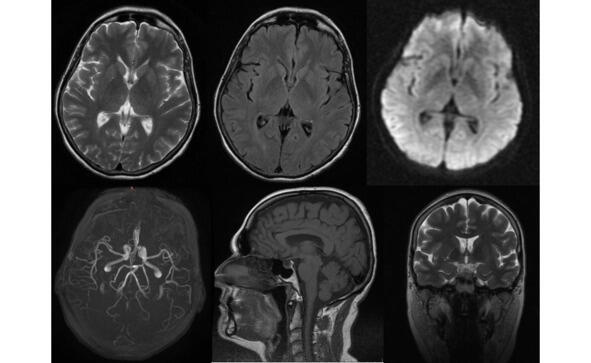

Изменения, выявляемые у пациентов с БП при проведении компьютерной томографии (КТ) и/или МРТ в стандартных режимах являются весьма неспецифичными. Преимущественно по данным нейровизуализации выявляется различной степени выраженности уменьшение объема вещества головного мозга: конвекситальная атрофия корковых отделов мозга, расширение желудочковой системы, которые не являются патогномоничными признаками этой патологии (рис. 13).

Рис. 13. Пример МР-томограмм пациентки 59 лет с БП.

Боковые желудочки мозга не расширены, симметричны (D=S). III-й и IV-й желудочки обычной конфигурации и размеров. Супраселлярная цистерна пролабирует в полость турецкого седла, остальные базальные цистерны не изменены. Субарахноидальные ликворные пространства неравномерно расширены по конвекситальной поверхности в проекции лобных, теменных долей и Сильвиевых щелей. Незначительно расширены периваскулярные пространства Вирхова-Робина по ходу пенетрирующих сосудов. Срединные структуры не смещены. Вертикальный размер гипофиза  до 0,3 см, сохраненная ткань гипофиза имеет обычный МР сигнал.

Более выраженные МР-признаки атрофии отмечаются у пациентов с акинетикоригидной формой заболевания, а также при наличие в клинической картине значительных когнитивных нарушений. Выраженность атрофии нарастает и по мере увеличения тяжести и продолжительности заболевания. Так, при длительности БП до 3 лет атрофия выявляется у трети пациентов, а при длительности свыше 6 лет возрастает более чем в 2 раза и отмечается у 78% пациентов.